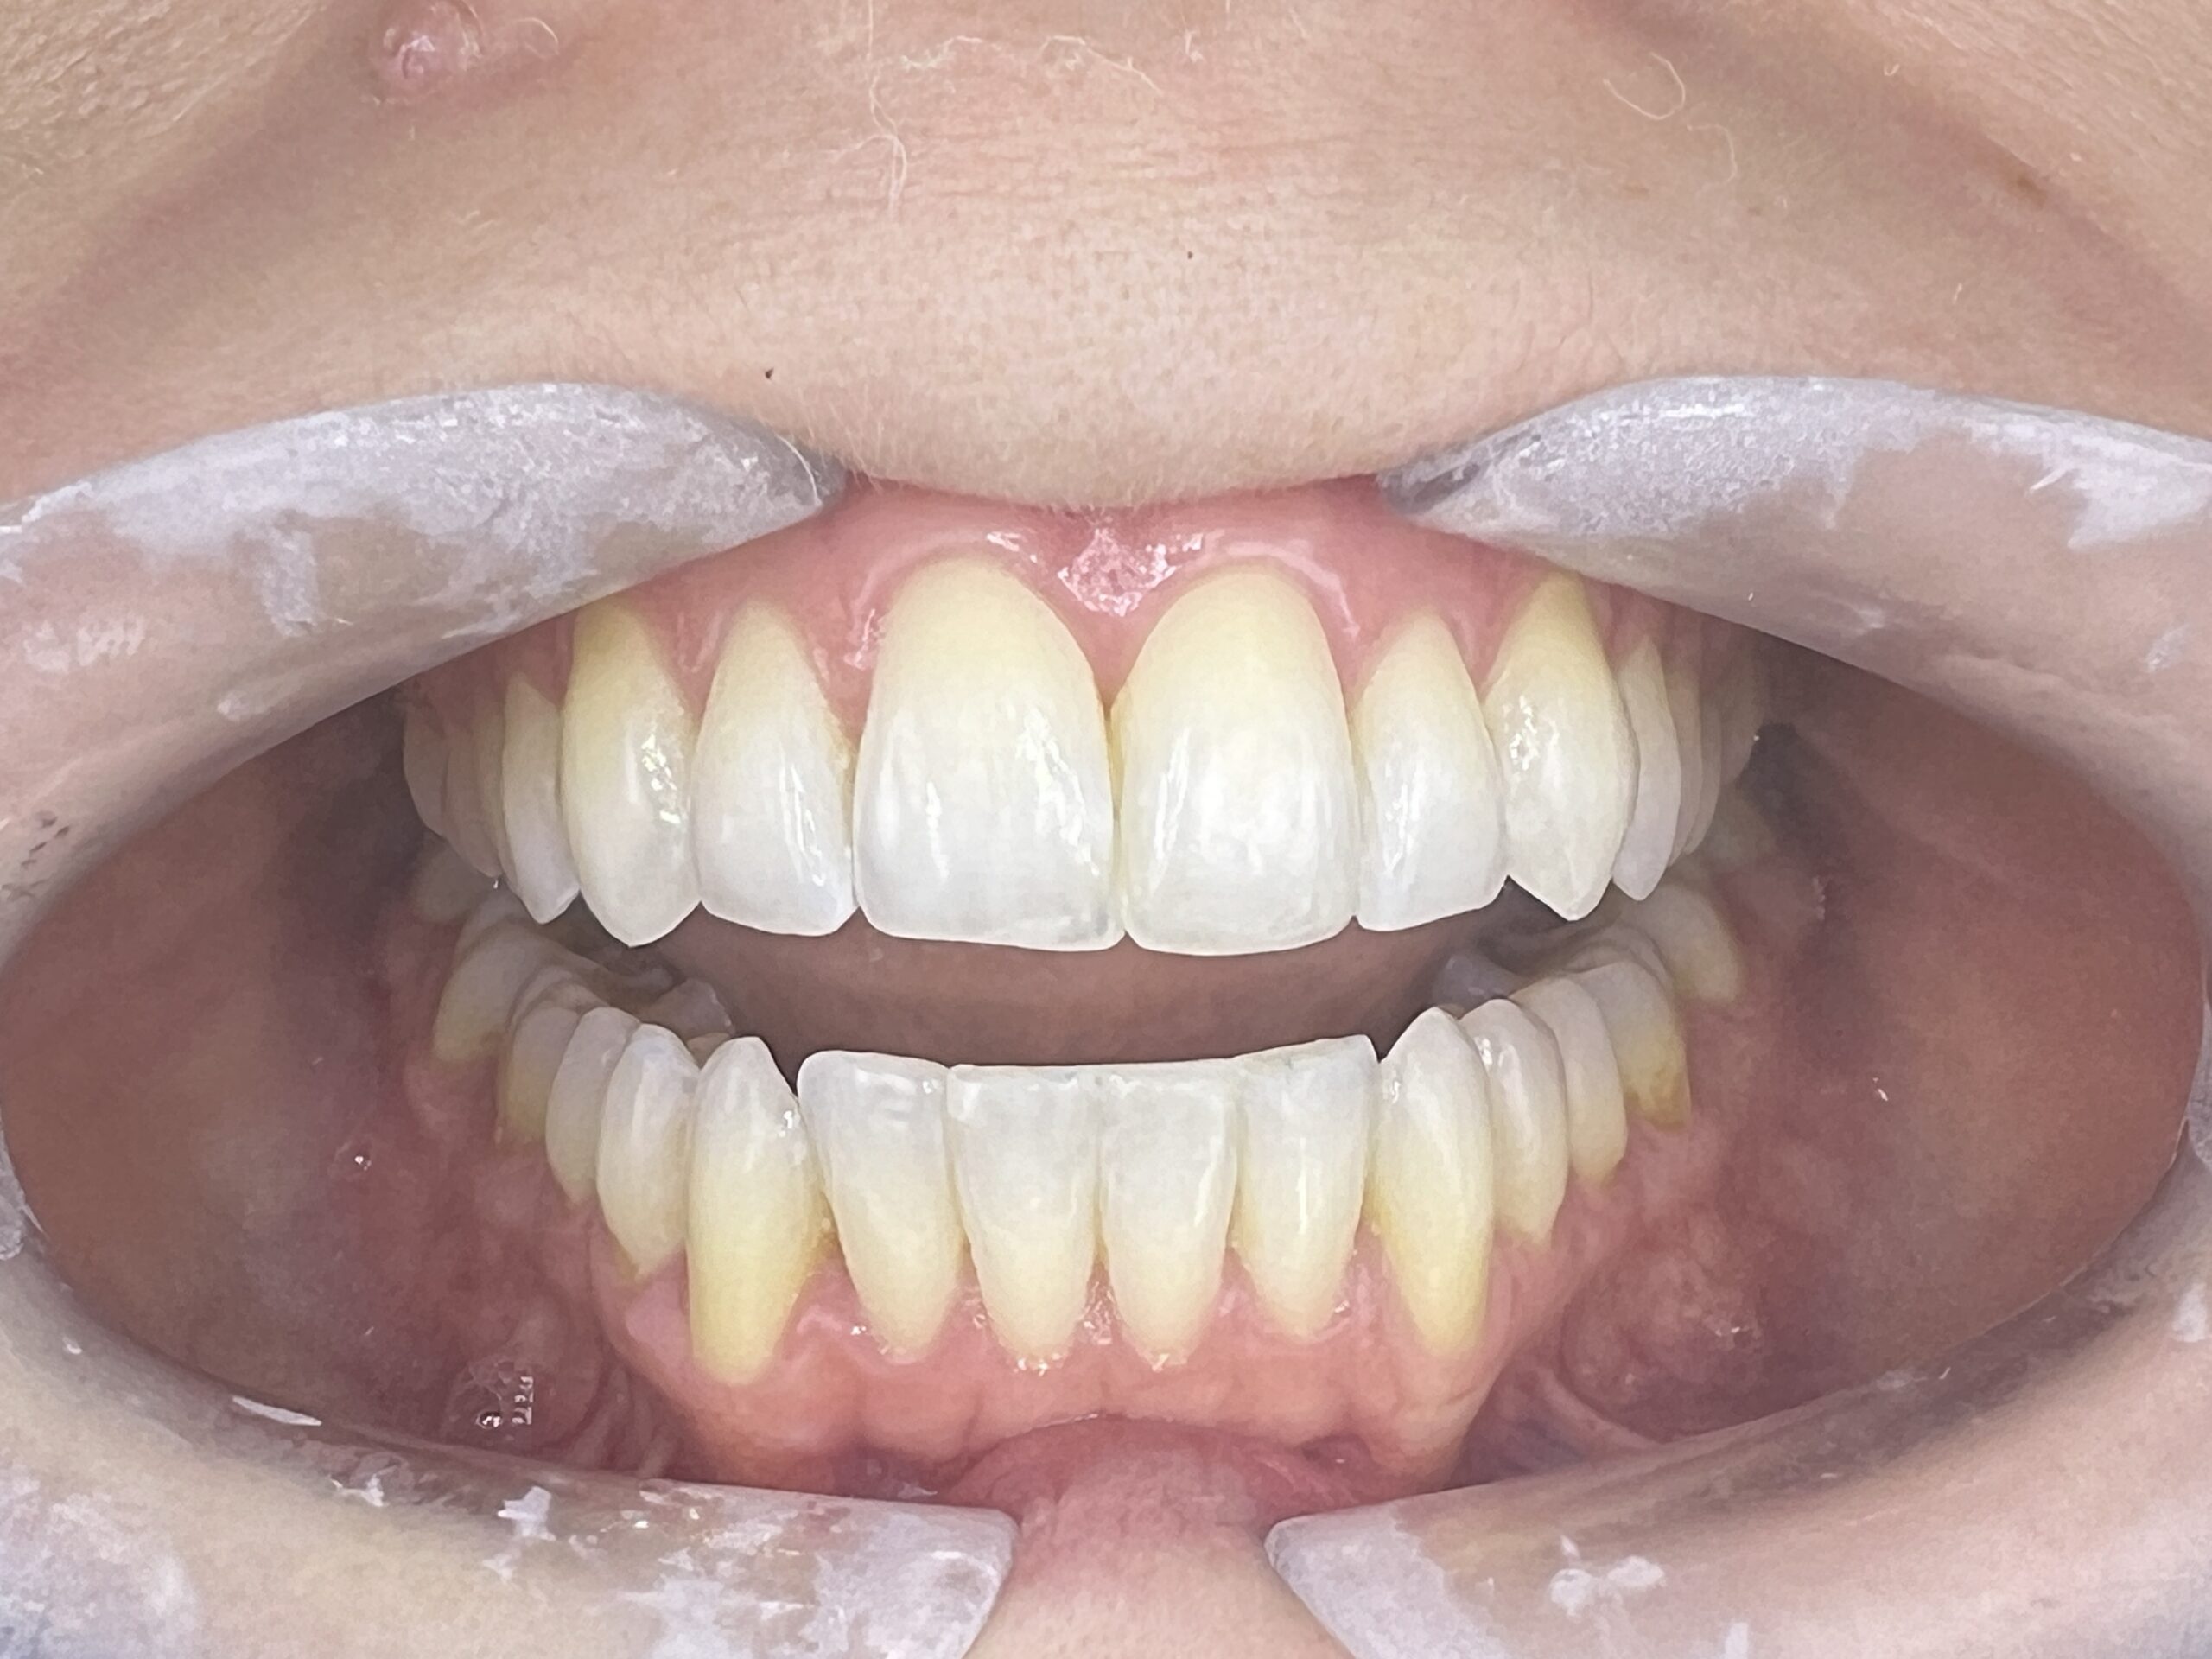

Clinical situation before

Clinical situation after. Bright shade in teeth 12 and Natural in 13 and 23